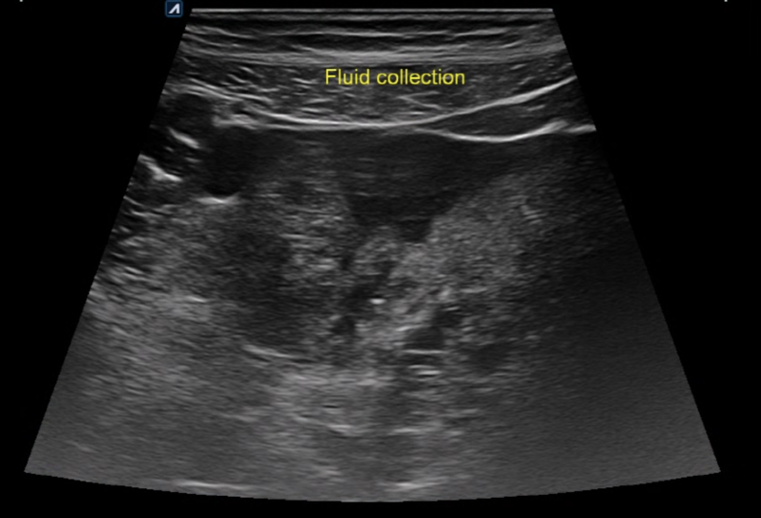

생리통으로 오인하여 내원한 복통 환자의 초음파.

하복부의 장관 부종이 확인됩니다.

골반에 복수 의심 소견이 관찰됩니다.

*난소종양 의심 소견 확인되어 대학병원 의뢰되었습니다.